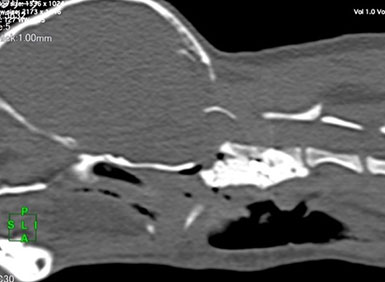

頸部・胸腰部椎間板ヘルニア

CT・MRI による画像診断で、椎間板の脱出/突出、脊髄圧迫の有無を確認し、保存療法または外科療法を実施しております。

椎間板摘出術

脊髄を圧迫している椎間板物質を摘出することで、歩行機能が回復します。